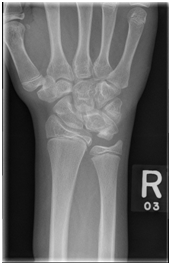

The X-rays showed the presence of a large bone tumour arisen from the lunate bone, not showing the actual involvement of the tumour in the carpal joints (Figure 2A); the subsequent CT scan confirmed the more accurate extension of the mass showing how the osteochondroma expanded dorsally and proximally, reducing and invading the ulno-carpal space (Figure 2B &2C), and also in the lateral view was easy to see how the deformed lunate had an expansion of the volar rim up to the neck of the capitate, reducing the midcarpal motion as well (Figure 2D).

Figure 2A PA x-ray showing the osteochondroma of the ulna